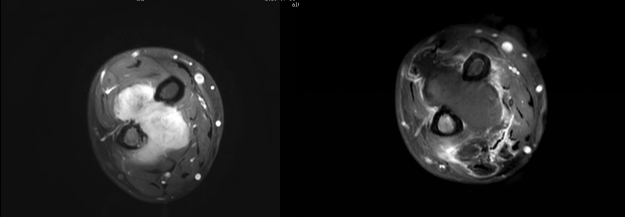

患者3年前無明顯誘因下出現右前臂腫脹,伴壓痛,程度不劇,至當地醫院就診,查MR提示:右前臂軟組織腫塊。遂行手術。術后病理示:右腕部梭形細胞腫瘤或瘤樣病變,結合免疫組化及影像學結果,考慮侵襲性纖維瘤病。2年前患者無明顯誘因下出現右前臂腫脹,隱痛,夜間加劇,伴皮溫升高,遂至我院就診,超聲提示右前臂尺橈骨間腫塊,考慮復發可能。患者行腋窩局部神經阻滯下HIFU治療,術后復查腫塊消融約90%。

侵襲性纖維瘤 治療前MRI增強,治療后1天MRI增強